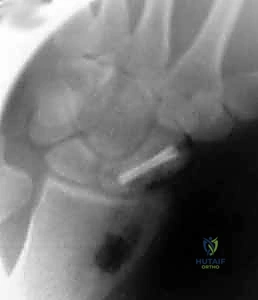

- الأشعة السينية المتقدمة (X-rays): أخذ صور للرسغ من زوايا متعددة ومخصصة (Scaphoid views) لرؤية العظم بوضوح. تُظهر الأشعة السينية في حالات عدم الالتئام وجود فجوة واضحة بين جزئي العظم، وتصلب (Sclerosis) في حواف الكسر، وربما تكون أكياس عظمية (Cysts).

- التصوير المقطعي المحوسب (CT Scan): يُعد الأداة الذهبية لتقييم هندسة العظم. يوضح الـ CT Scan شكل العظم بدقة ثلاثية الأبعاد، ويقيس زاوية التشوه المحدب (Humpback)، ويساعد الجراح في تحديد حجم ونوع الرقعة العظمية المطلوبة بدقة مليمترية قبل الدخول إلى غرفة العمليات.